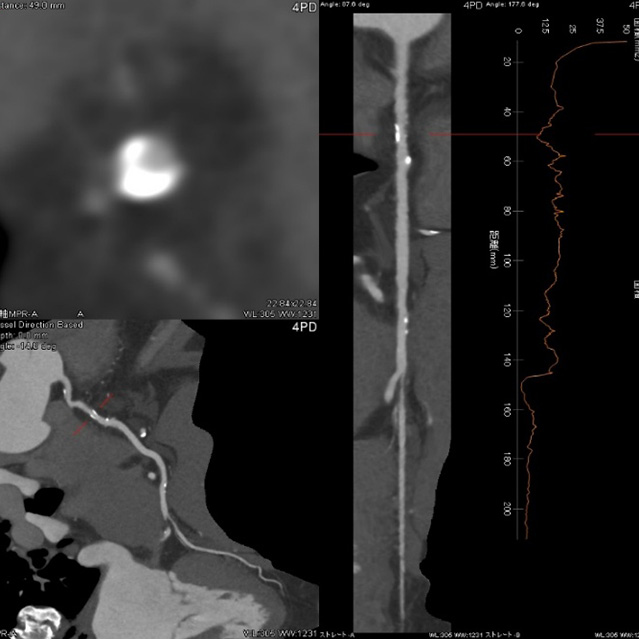

64列 MDCT Aquilion CX (canon)

80列 MDCT Aquilion PRIME (canon)

80列 MDCT Aquilion PRIME SP(canon)

大きなトンネルの中に体を入れて、X線をあてて体の輪切りの写真を撮ります。CT検査には、単純CT検査と、造影剤を注射して撮影する造影CT検査があります。